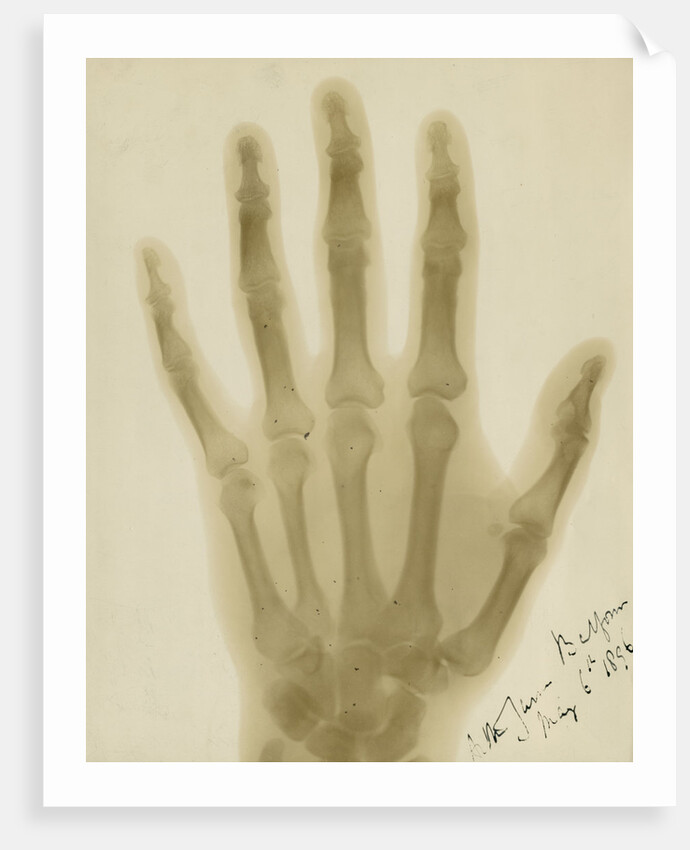

Product images of X-ray photograph of the hand of Arthur James Balfour

Product details X-ray photograph of the hand of Arthur James Balfour

X-ray photograph of the hand of Arthur James Balfour

Alan Archibald Campbell Swinton

X-ray image of Lord Balfour's left hand showing its bones and a faint outline of the soft tissue of his fingers, darkening towards his hand and wrist. Signed and dated on the print, below the thumb: 'Arthur James Balfour May 6th 1896'. Inscribed in pencil verso: 'Taken by A.A.Campbell Swinton at the Royal Society's Soiree held on 6 May 1896.' With a paper label verso, stamped: 'FROM MR.SWINTONS PHOTOGRAPHIC LABORATORY, 66, VICTORIA STREET, S.W.'. Annotated in ink below this 'negative no.77.' The gift of prints is noted in Council Minutes: 'Mr.A.A.C.Swinton has presented the Society with a series of Rontgen 'Photographs' taken at the May Soiree, and thanks have been given to him for them.' [Royal Society Council Minutes, Printed, CMP/7, meeting of 29 October 1896, p.294.] Arthur James Balfour, 1st Ear of Balfour, was elected as a Fellow of the Royal Society in 1888 and served as a Vice-President 1912-1914.

Original: radiograph print. 1896

- Image ref: RS-9839

- The Royal Society